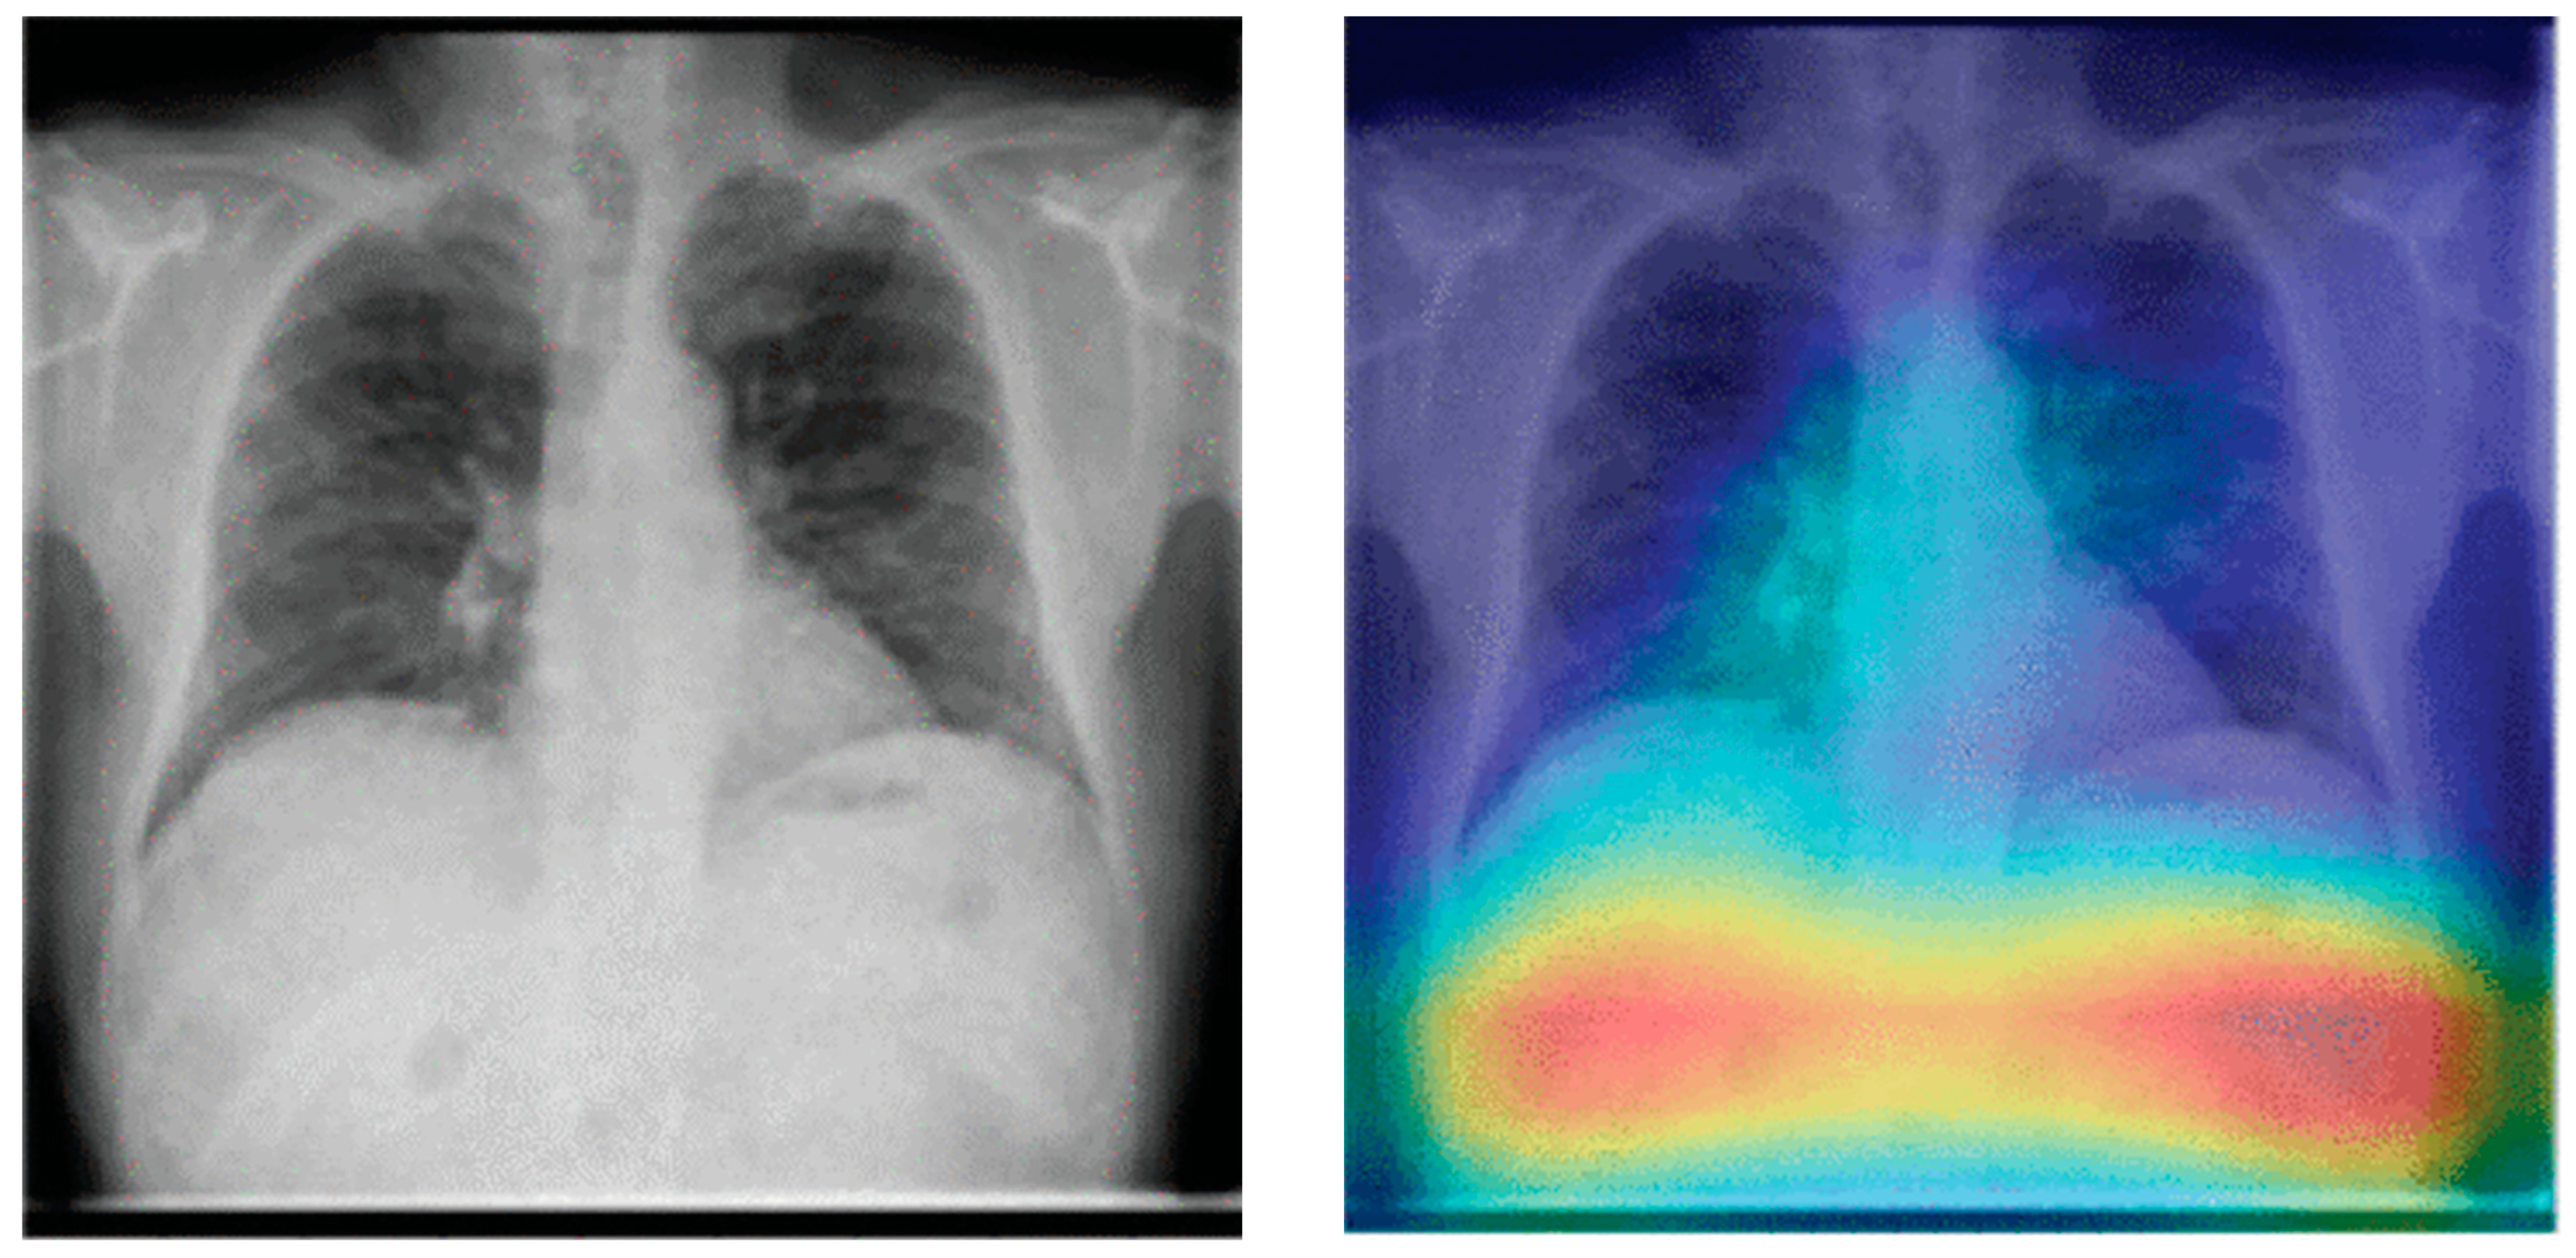

- Selvaraju, R.R.; Cogswell, M.; Das, A.; Vedantam, R.; Parikh, D.; Batra, D. Grad-CAM: Visual Explanations from Deep Networks via Gradient-Based Localization. Int. J. Comput. Vis. 2020, 128, 336–359. [Google Scholar] [CrossRef]